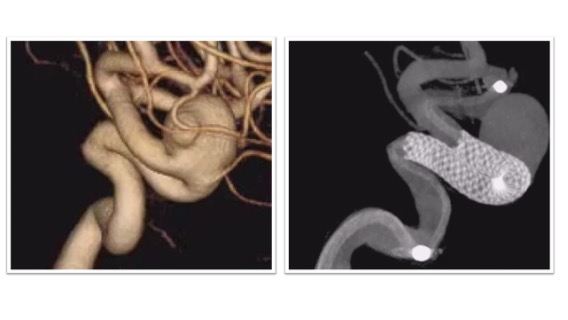

ステント併用コイル塞栓術治療実例(*患者様の許可を得て掲載しています)

内頸動脈後交通動脈分岐部(ICPC)動脈瘤

ICPCの動脈瘤へのステント併用コイル塞栓術後の脳血管撮影画像とレントゲンです。血管撮影画像から脳血管ステントを併用することで動脈瘤が塞栓され、動脈瘤から分枝している後交通動脈の血流は温存されている様子がわかります(図左 血管撮影)。内頸動脈で展開されたステントが壁となることで動脈瘤に充填された塞栓用コイルが内頸動脈や後交通動脈側にはみ出さぬようになっています(図右 レントゲン)。